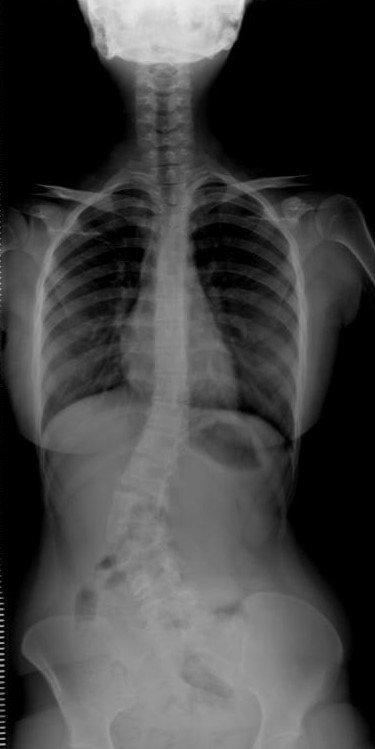

Toplumda her 100 kişiden 2 ila 4'ünde, kız çocuklarında ise erkeklere oranlara 8-10 kat daha fazla görülen skolyoz, nefes almadan, ayakta durmaya, başı çevirmekten, bedeni döndürmeye kadar çeşitli fonksiyonları olan omurgada genellikle S ya da C harfi şeklinde yana doğru eğilmelerle karşımıza çıkıyor. Manisa'nın Akhisar ilçesinde hayatını sürdüren 23 yaşındaki Eda Ar da doğuştan kaynaklanan skolyozu nedeniyle duruşunda dengesizlik yaşıyordu. Yaşı büyüdükçe ağrıları da artan genç kız doktora gitti.

Eda'nın omurgasındaki eğriliğinden doğuştan kaynaklandığını anlatan Medicana International İzmir Hastanesi'nde görevli Ortopedi ve Travmatoloji Uzmanı Doç. Dr. Mutlu Çobanoğlu, "Doğuştan kaynaklanan skolyoz, genellikle ilerleyici tipte oluyor. Çocuk büyüdükçe kendini göstermeye başlıyor. Dışarıdan bakılınca gözükmeyebiliyor. Eda'daki gelişim kusuru omurgasını belli bir tarafa doğru itmişti. Duruşunda dengesizlik meydana geliyordu. Yaşı daha küçükken ağrısı muhtemelen olmuyordu ancak büyüdükçe ağrıları olmaya başladı. Hastadaki skolyozun derecesi ve hastada meydana getirdiği şekil bozukluğuna göre tedavi seçenekleri var. Her skolyoz mutlaka ameliyat olmalı diye bir durum söz konusu değil" diye konuştu. Doç. Dr. Çobanoğlu, skolyozun tedavi edilmediği durumlarda, kişinin solunum problemleri yaşayabildiğini, omurgada dengeli bir yük dağılımı olmadığı için artan ağrılara bağlı olarak kireçlenme olabileceğini ve tüm omurganın bu durumdan etkilenebileceğini de sözlerine ekledi.